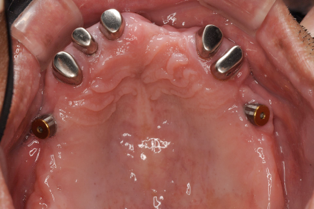

この方は結局、all on 4 を応用し、奥歯に両側2本のインプラントを傾斜埋入して、それにマグネットをつけました。これなら骨移植をせずにインプラントが可能になり、3ヶ月ほどで終了できます。

マグネットをつけているので大幅に義歯の面積を縮小することが可能になりました。